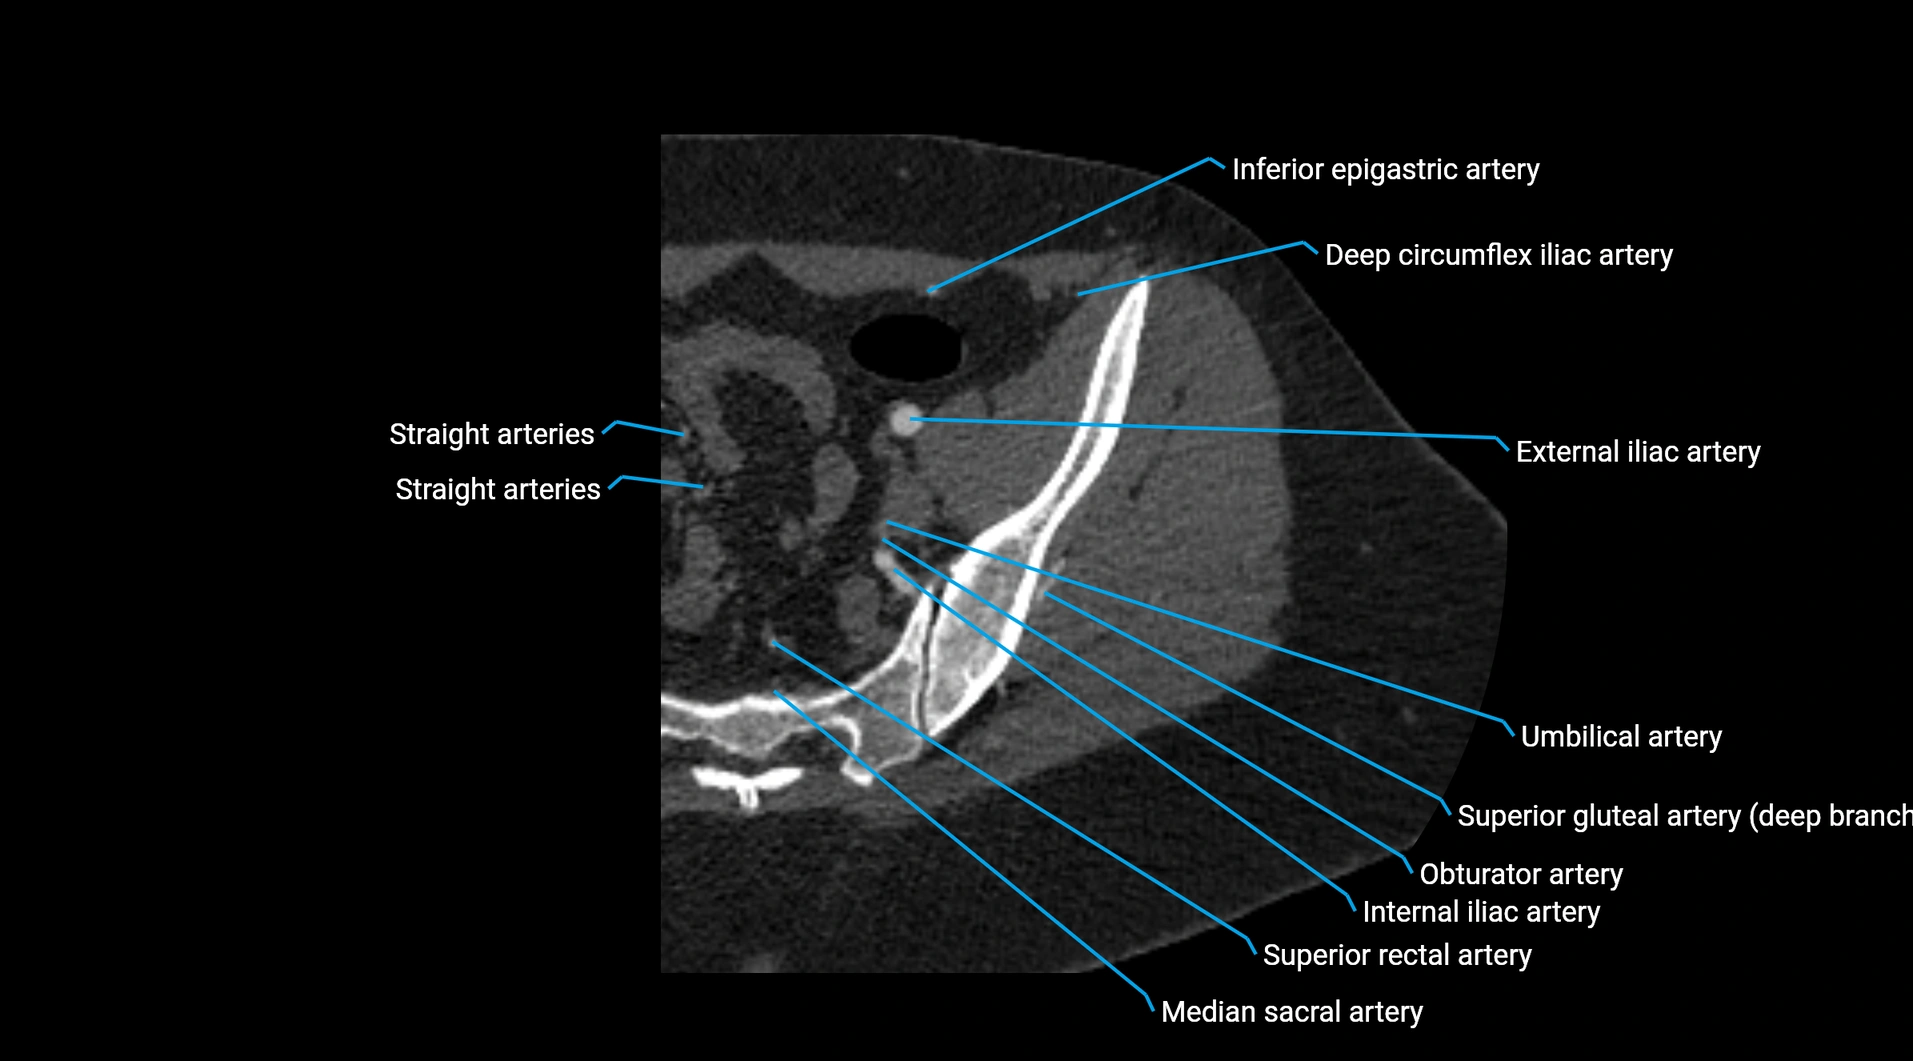

CT images

image

Contrast-enhanced CT (CTA):

• Gold standard for abdominal aortic imaging

• Provides excellent detail of lumen, wall, aneurysm, thrombus, and branch vessels

• Multiplanar and 3D reconstructions help in aneurysm measurement, stent graft planning, and dissection evaluation

• Parietal branches: inferior phrenic arteries, lumbar arteries, median sacral artery

• Terminal branches: right and left common iliac arteries